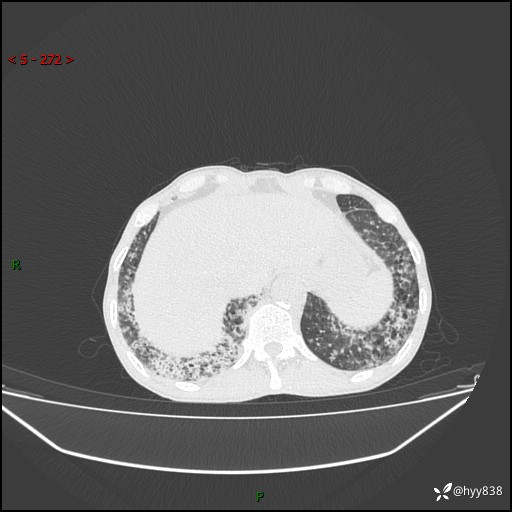

胸部CT平扫